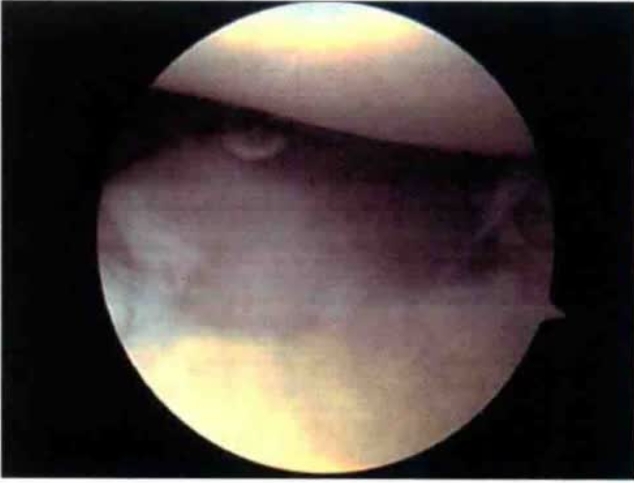

镜下可见桡侧腕短伸肌腱在起点偏远处存在不同程度的退行性变与损伤,其质地、颜色、完整性均与正常肌腱不同(图8)。

图8 镜下病变组织

Baker等将损伤分为3类:第1类为关节完整;第2类为关节囊呈线性撕裂;第3类为关节完全撕裂与退缩,但未发现损伤类型与预后有关。检查时如发现肱桡关节存在软骨退行性变、邻近区域滑膜增厚、出现滑膜皱襞(是引发疼痛的原因之一)需一并处理(图9)。

图9 肱骨外上髁炎合并肱桡关节滑膜皱襞形成